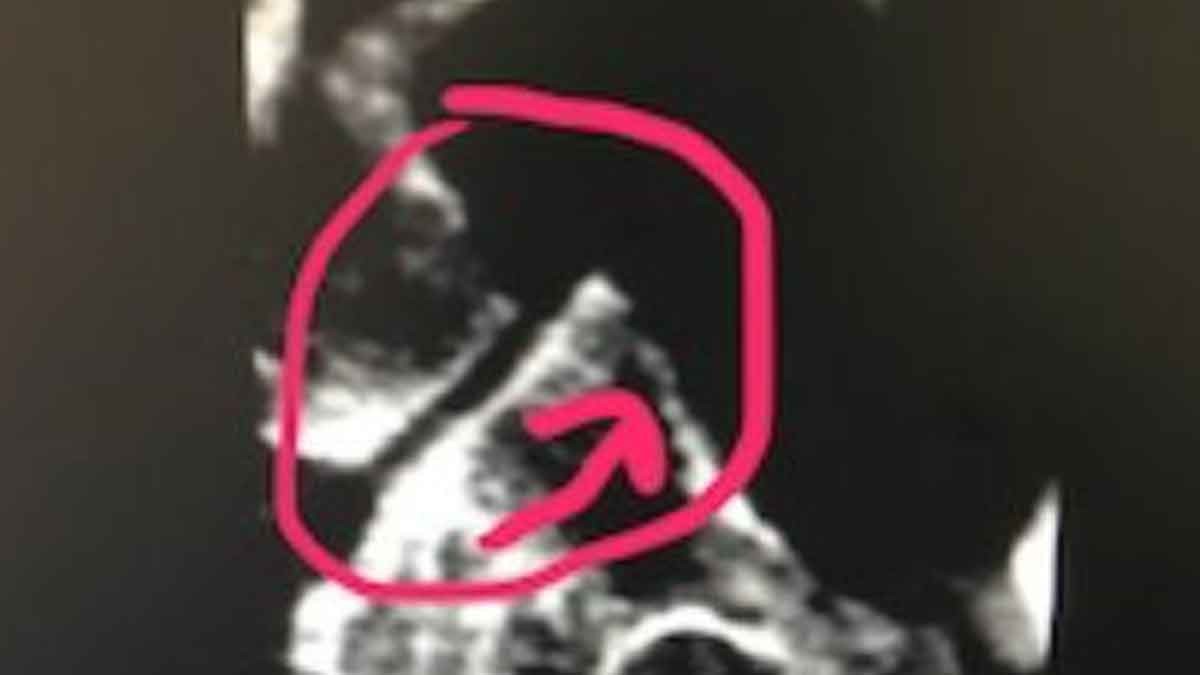

CLOSE LOOK AT C3, C4 ARTICULATION ON RIGHT

Observe the articulation of C2-C3. The joint of c-2 has moved forward(arrow) along the c-3 joint below. This image allows the Doctor to measure exactly how the joint is built(angle) and direct a force in the opposite direction of the misalignment to correct it.